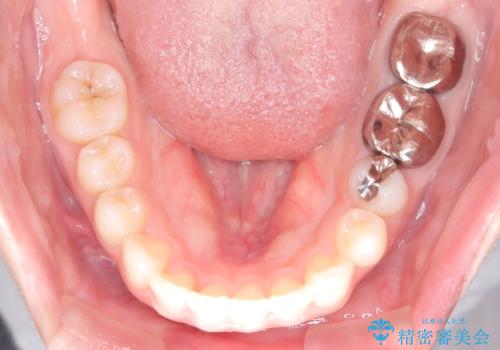

- 前歯が出ていることを主訴に来院された患者様です。

抜歯を希望されなかっため、臼歯部の遠心移動やIPRを行い配列を行っています。

抜歯をしていない矯正となるため、口元に大きな変化は認められません。